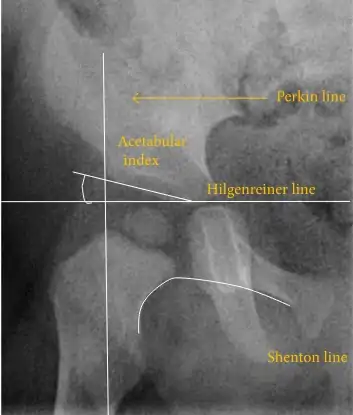

The most useful lines and angles that can be drawn in the pediatric pelvis assessing DDH are as follows:[1]

Figure 2C. AP view of a patient with left hip effusion secondary to trauma showing widening of the medial joint space.[1]

Figure 2C. AP view of a patient with left hip effusion secondary to trauma showing widening of the medial joint space.[1]